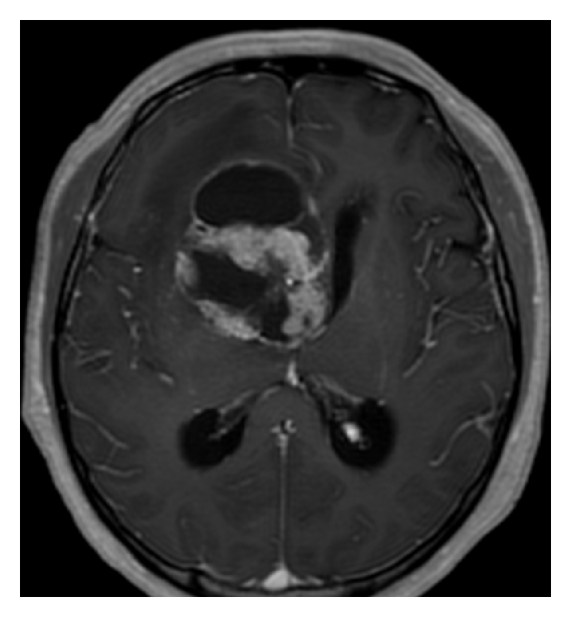

A 42-year-old Japanese man was admitted to our hospital for headache and nausea. These symptoms had progressed for 4 days before admission, and he was gradually unable to walk steadily. Magnetic resonance imaging (MRI) revealed a mass lesion with marked cyst components. The lesion had a maximum diameter of 58 mm (Figure 1). T1-weighted images (WIs) after gadolinium administration showed ring enhancement. T2WIs showed slight edema around the lesion. Proton magnetic resonance spectroscopy (1H-MRS) analysis of the nodule showed an increased ratio of choline to creatine and an apparent peak for lactate, which is strongly correlated with tumor malignancy. In contrast, the peak for N-acetylaspartate (NAA) was within the background noise level (Figure 2). The neuroimaging diagnosis was a primary malignant brain tumor such as glioblastoma multiforme (GBM) or a metastatic brain tumor. The patient underwent subtotal removal of the lesion via a fronto-temporal craniotomy.

(a)

(b)

(c)

(d)